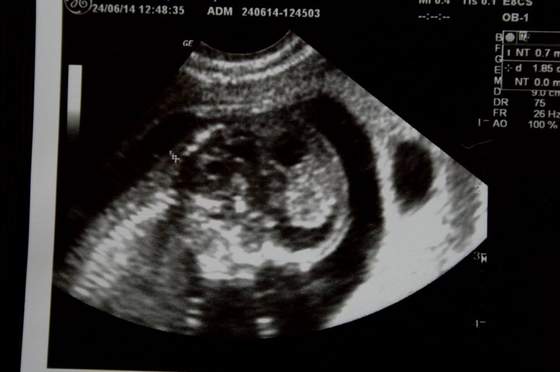

Z maleństwem wszystko ok, rośnie (ma już prawie 6cm, a na ostatnim usg 29 maja miało 164mm), wierzga jak szalone, widać super już rączki, nóżki,narządy w środku i w czasie badanie łapało za pępowinę :-)

FasolinkaZobacz załącznik 630536Zobacz załącznik 630538